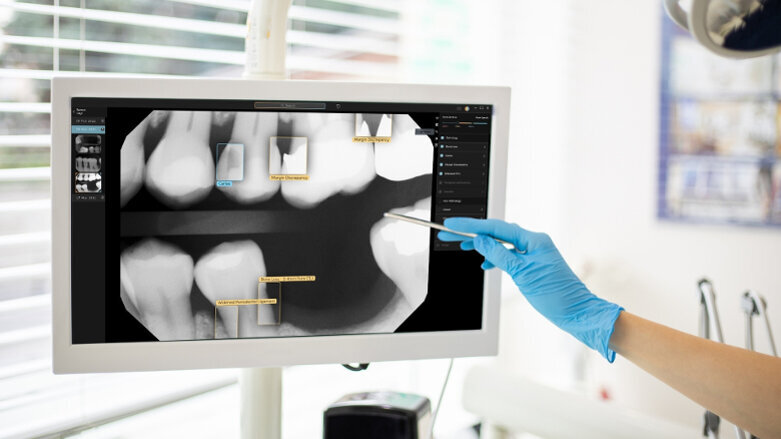

Pearl refers to Second Opinion as a computer vision platform that can identify and measure an array of pathologies, existing restorations and anatomy in dental radiographs. The company explained in a press release that Second Opinion applies radiological computer vision that highlights potential areas of interest and provides dentists with a second set of eyes when interpreting radiographs. It helps “dentists ensure that patient care decisions are based on the strongest foundation possible and to give dentists a new level of assurance when communicating findings to patients,” the company said.

“Our Second Opinion technology enables dentists to perform their job more confidently, see more patients and ensure a higher standard of need-based care”

– Ophir Tanz, CEO, Pearl

According to Pearl, patients will also benefit from the technology. “Patients in Australia and New Zealand will soon have the opportunity to experience AI during dental appointments and gain assurance that they are receiving the best diagnosis and treatment plan based on their individual needs,” Ophir Tanz, CEO and founder of Pearl, commented in the media release. “Our Second Opinion technology enables dentists to perform their job more confidently, see more patients and ensure a higher standard of need-based care. All of these factors are driving growth and better patient outcomes in dentistry,” Tanz added.